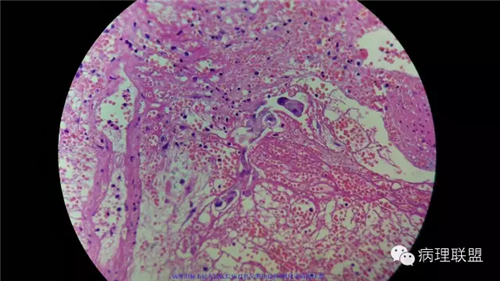

病例2

女性,60岁,结肠腺瘤活检。有一灶腺体突破粘膜肌,腺体无明显异形。

(注:病例由岳阳病理吴龙云提供 致谢!)